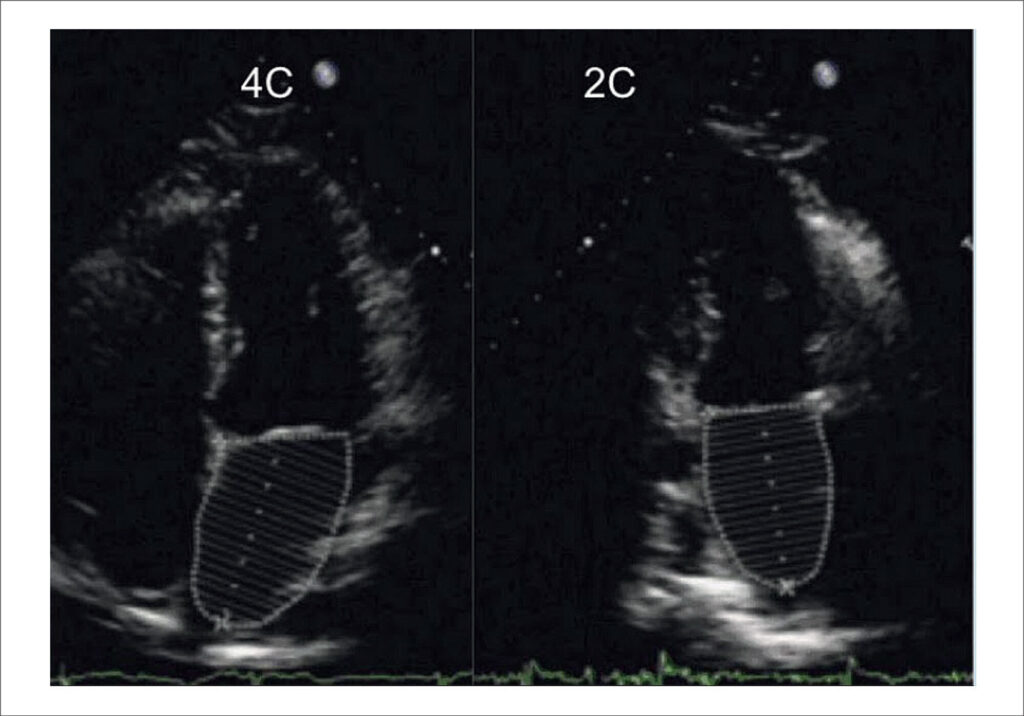

Therefore, the early identification of markers of sickle cell cardiomyopathy using echocardiographic parameters (Central Illustration) is essential for the appropriate management of the cardiovascular condition in these patients.

This review provides a comprehensive overview of the use of echocardiography in pediatric patients with SCD, highlighting the main characteristics of the condition and the importance of regular follow-up.